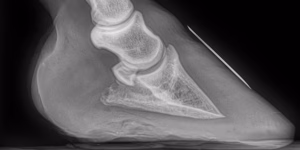

Hoof Abscesses in Horses

Abscesses in a horse’s hoof can be common during winter. Learn how to spot and manage a horse abscess in the foot.

Laminitis in Horses

Learn about laminitis in horses, including its causes, symptoms, treatment options, and prevention tips. Read more about this equine disease today.